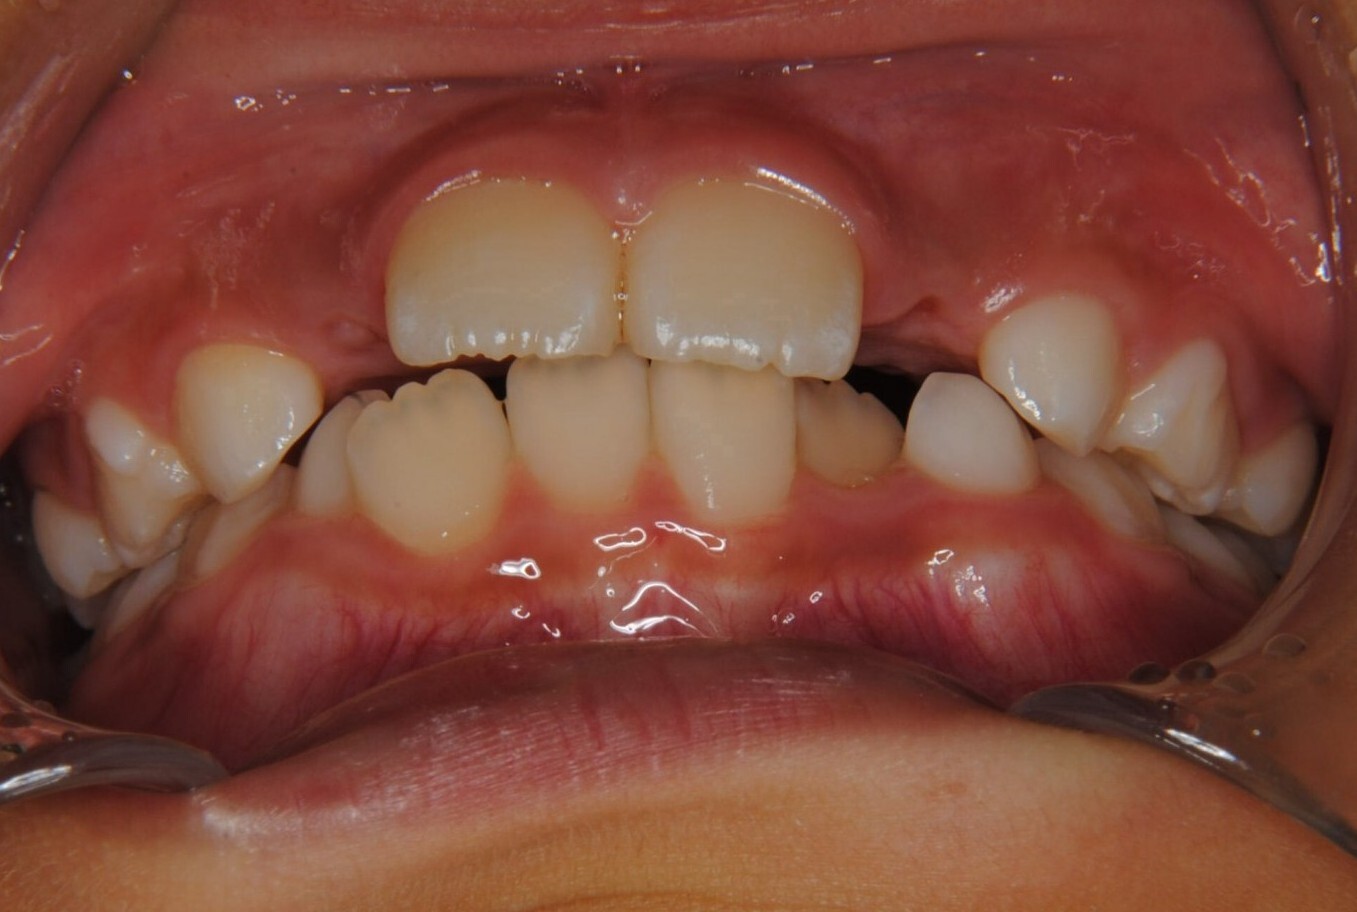

①主訴:下の前歯のデコボコ

②診断名:Ⅰ級叢生

③年齢:初診時(左写真)8歳6か月、終了時(右写真)11歳4か月

⑧リスクと副作用:特に大きなリスクや副作用はありませんでした。拡大床装着直後は違和感があったようですが、特に痛みを感じることなく6.5mmまで拡大できました。その後永久歯への生え変わりも順調で、ほぼ正常な咬み合わせになりました。この後11歳4か月まで観察し、7番目の奥歯である12歳臼歯がきちんと咬んだので終了となりました。